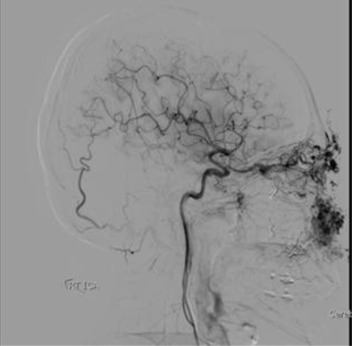

Internal carotid artery run showing arteriovenous malformation feeder vessels ...

Figure 2.

Internal carotid artery run showing arteriovenous malformation feeder vessels from the ophthalmic artery.

A 35-year-old man first presented with a progressive swelling of his left eye lid for 10 years, and was treated then with embolization. His vision at that time was normal. He presented again 5 years later with a large nonpulsatile proptosis and blindness of his left eye, dilated tortuous vessels over the scalp and forehead (Fig. 1), and life-threatening epistaxis requiring repeated nasal packing. An urgent cerebral angiogram revealed an extensive left intraorbital and hemifacial AVM supplied by the ophthalmic, maxillary, facial, lingual, and superficial temporal arteries from both sides (Figs. 2 and 3) with no contrast extravasation noted. Both sphenopalatine arteries were empirically embolized with Histoacryl [n-butyl-2-cyanoacrylate (NBCA)] to prevent further episodes of epistaxis. Magnetic resonance imaging (MRI) showed a heterogeneously enhancing left orbital mass extensively involving the left periorbital and hemifacial area, containing dilated tortuous vessels with a “signal void” ( Fig. 4). A multidisciplinary team decision resulted in preoperative embolization by the interventional radiologist using Onyx 18 (ev3, Irvine, CA, USA), a nonadhesive liquid embolic agent consisting of ethylene vinyl alcohol copolymer dissolved in dimethyl sulfoxide and micronized tantalum powder, via a sonic detachable microcatheter (Balt Extrusion, Montmorency, France), followed by radical surgery the next day.